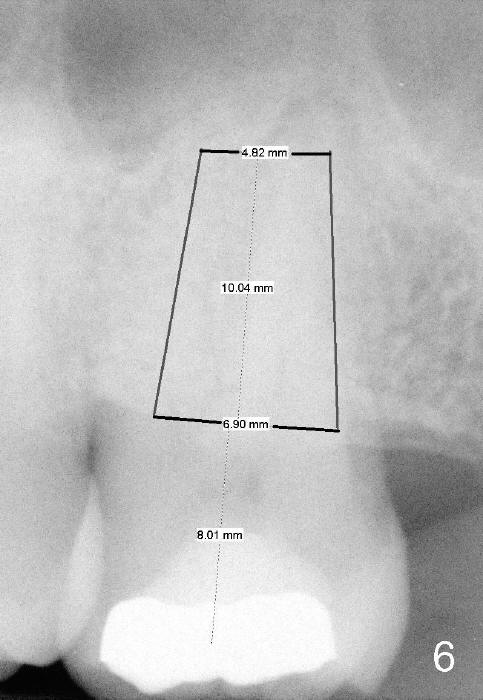

A 52-year-old black man fails to return to finish root canal therapy for the tooth #15; ultimately it is non-salvageable (Fig.1-3).  The tooth has 3 basically fused roots (Fig.4 black (buccal) and red (palatal) outlines), above which is the sinus septum (*).  By inserting an immediate implant into the sinus septum, primary stability should be high (Fig.5 vs. 6).